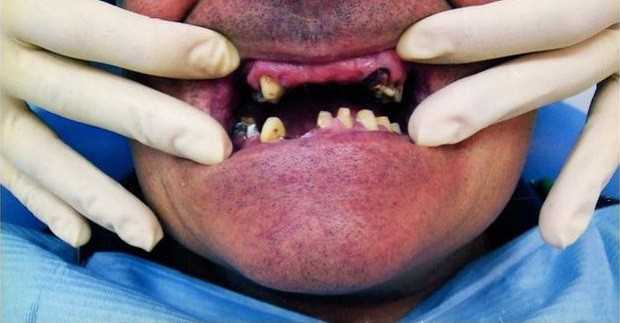

КАРАТ: работы специалистов (5)